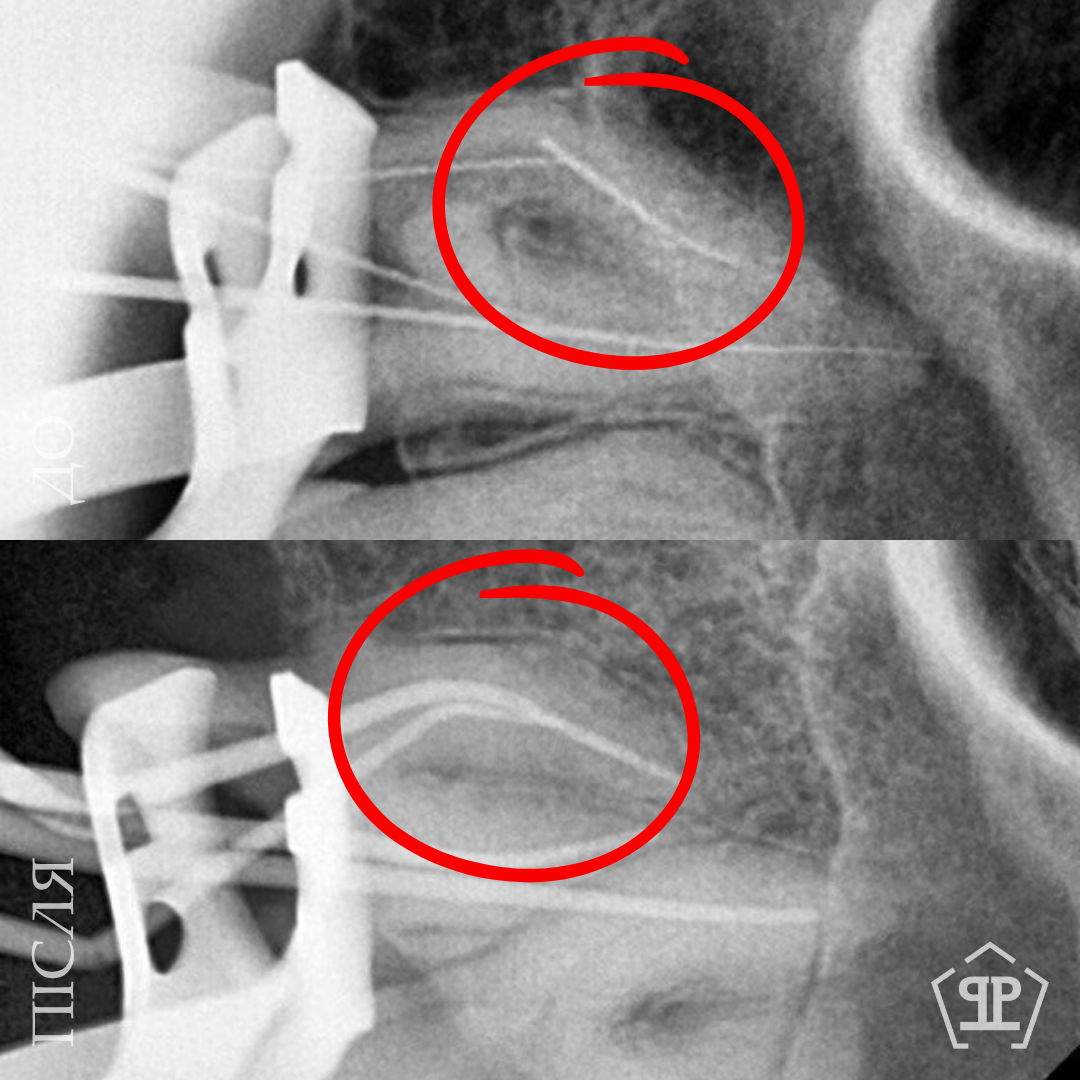

Перелечивание с удалением двух переломанных инструментов. Пациент обратился с осложнением предварительного эндодонтического лечения. В каналах были обнаружены два переломанных инструмента. Выполнены их удаление и пломбирование каналов с соблюдением современных эндодонтических протоколов.